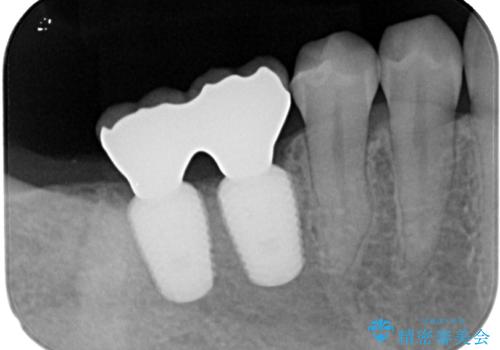

スペースが整った段階で、右下の第一大臼歯と第二大臼歯にインプラントを埋入。

その後、挺出していた右上第一大臼歯と第二大臼歯に装着されていた銀歯についても、審美性と適合性の向上を目的に、オールセラミッククラウンにやり替えました。

これにより、より自然で美しい見た目と、高い精度の咬合が得られています。